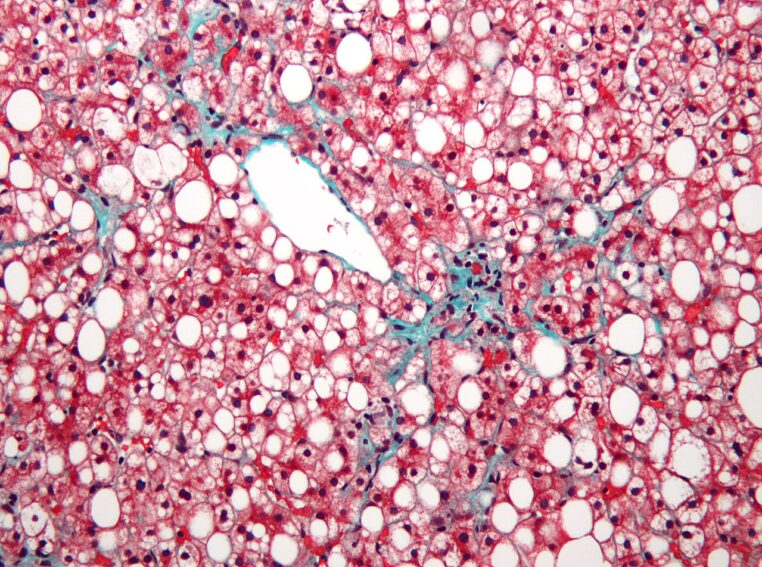

MASLD, NAFLD, « foie gras » : de quoi parle-t-on exactement ?

Depuis 2023, plusieurs sociétés savantes internationales ont acté une évolution de la terminologie : NAFLD est progressivement remplacé par MASLD (metabolic dysfunction–associated steatotic liver disease), et NASH par MASH. L’objectif est double : mieux refléter le rôle central des facteurs métaboliques (surpoids, diabète de type 2, dyslipidémie, hypertension) et sortir d’une définition uniquement « par exclusion » de l’alcool. Les sociétés européennes (EASL) et américaines (AASLD) expliquent ce changement, issu d’un consensus international.

En France, l’Assurance Maladie (ameli.fr) décrit la stéatose hépatique métabolique comme une accumulation de graisses dans le foie associée au syndrome métabolique, et rappelle qu’elle peut évoluer vers une inflammation puis une fibrose, voire une cirrhose chez une partie des patients. La SNFGE souligne aussi le rôle des facteurs de risque métaboliques dans la progression.